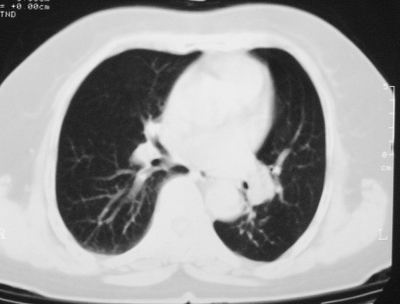

左下肺软组织块影,有分叶、毛刺、空泡及胸膜牵拉征,左下肺周围性肺癌。

左肺下叶周围型肺癌,支持!(软组织肿块+分叶+毛刺+空泡+胸膜凹陷征)

左下肺软组织密度影,可见分叶,边缘可见毛刺征,胸膜增厚,强烈要求左下肺周围型肺癌

左下肺后基底段实性肿块,周围有毛刺,病变周围有肺气肿,与降主动脉间有条带状影相连,病灶4年前查体发现,纵隔内未见肿大淋巴结。考虑.肺隔离症,建议增强扫描与周围型肺癌鉴别。